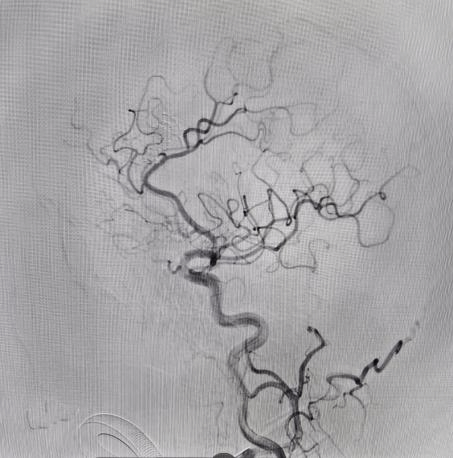

面对大动脉瘤且血管条件差的患者(腹主动脉S型迂曲,右侧颈总动脉II型牛角弓),以及颈内动脉多发动脉瘤的不同患者(C5-C7有5枚动脉瘤),吴全主任团队运用密网支架对症治疗,用一个支架巧妙解决大动脉瘤或多个动脉瘤难题,效果良好,患者短时间内快速恢复。

对于非责任动脉瘤的处理,医生们更是展现出专业与耐心。9个月前,患者动脉瘤破裂出血,当时造影发现2处动脉瘤,术中优先处理责任动脉瘤,待患者身体恢复后择期处理非责任动脉瘤。此次处理非责任动脉瘤,手术中造影,发现责任动脉瘤栓塞术后复发(3月前复查尚无),医生们当机立断,同期处理两个动脉瘤,省钱的同时,也成功为患者解除隐患。